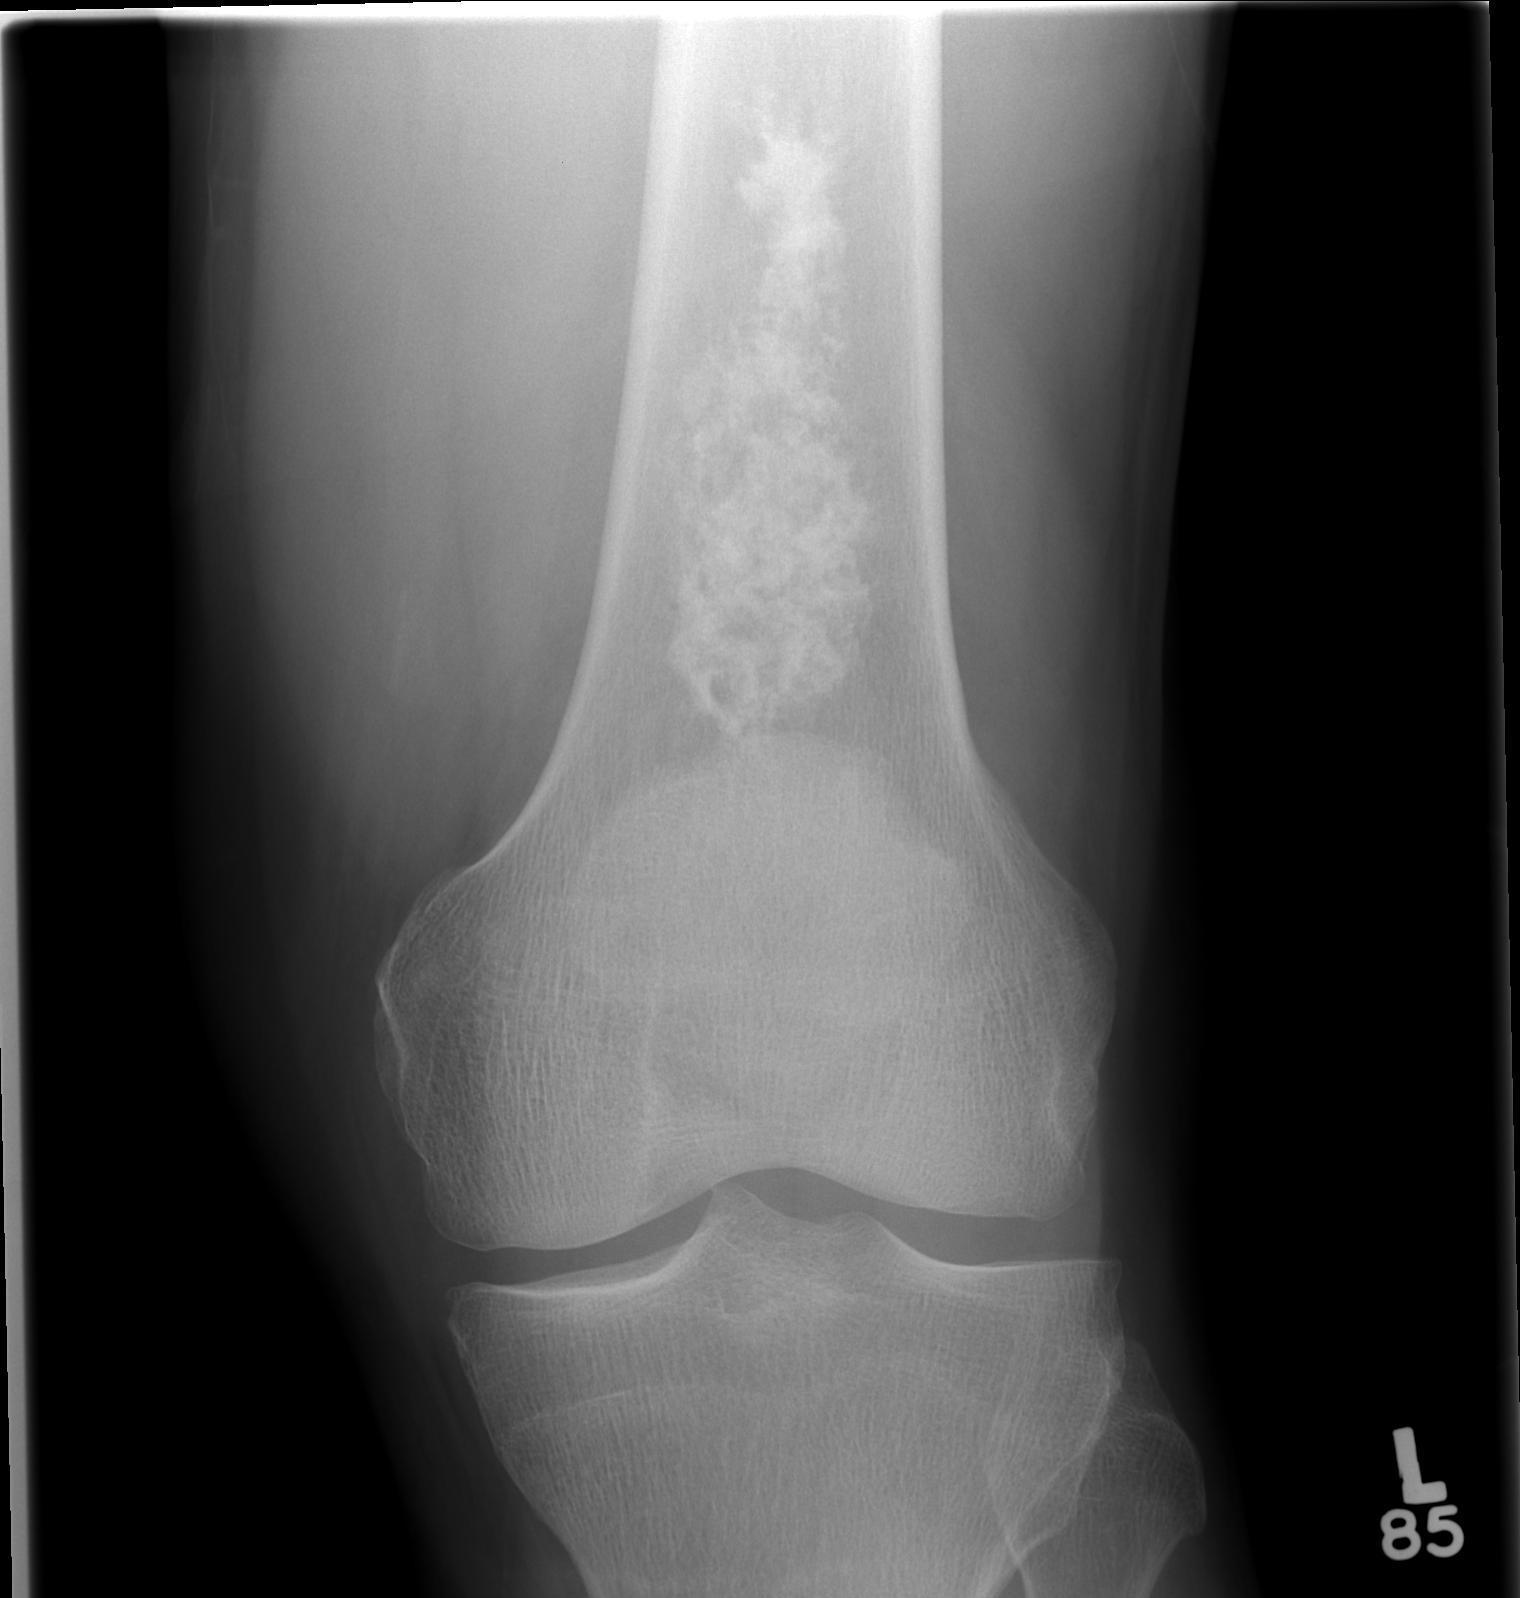

X-ray

Intralesional calcification - punctate, stippled calcification and broken rings

Differential diagnosis long bone with intralesional calcification

1. Enchondroma

2. Bone infarct

3. Chondrosarcoma

Large, central enchondroma